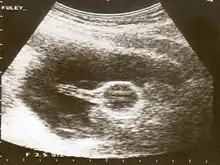

A Foley catheter can also be used to ripen the cervix during induction of labor. When used for this purpose, the procedure is called extra-amniotic saline infusion.[9] In this procedure, the balloon is inserted behind the cervical wall and inflated, for example with 30-80 mL of saline.[9] The remaining length of the catheter is pulled slightly taut and taped to the inside of the leg. The inflated balloon applies pressure to the cervix as the baby's head would prior to labor, causing it to dilate. As the cervix dilates over time, the catheter is readjusted to again be slightly taut and retaped to maintain pressure. When the cervix has dilated sufficiently, the catheter drops out.[10]